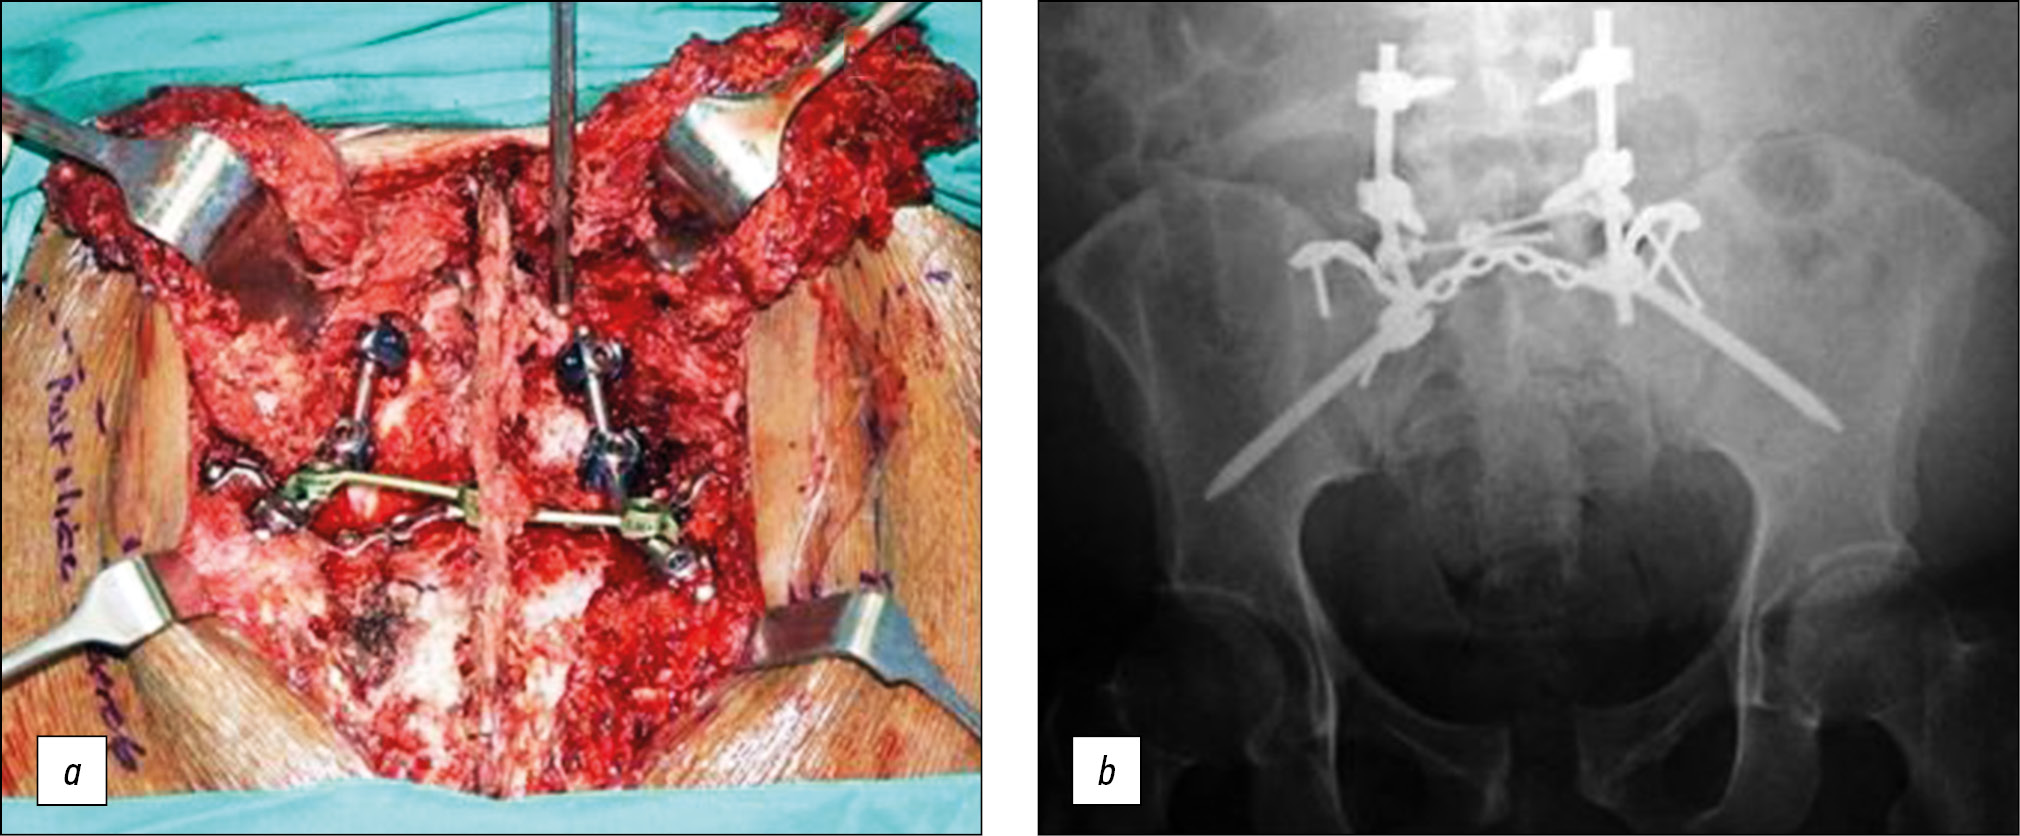

Техники позвоночно-тазовой фиксации позволяют соединить поясничный отдел позвоночника с подвздошной костью. Позвоночно-тазовая фиксация соединяет позвонки поясничного отдела с подвздошными костями при помощи педикулярных винтов и стержней. В случаях высокой степени нестабильности повреждения таза наиболее стабильную компоновку конструкции можно получить, соединив как позвонки LIV, так и LV с подвздошными костями с обеих сторон. В ситуациях, где нагрузка на конструкцию предполагается меньшей, может быть достаточно фиксации от позвонка LV до подвздошной кости с одной стороны [40]. Аналогичным образом подвздошных винтов может быть как по 1, так и по 2 и более с каждой стороны [41]. Если вышеупомянутая пояснично-подвздошная техника сочетается с подвздошно-крестцовыми винтами или пластиной, она образует узел триангулярного остеосинтеза (рис. 8), первоначально предложенный как односторонний, но также описанный и как двусторонний с большей стабильностью, представляющий собой наиболее устойчивый метод фиксации заднего полукольца таза [42].

Рис. 8. Триангулярный остеосинтез заднего полукольца таза [42]. a — интраоперационное фото, b — обзорная рентгенограмма таза.